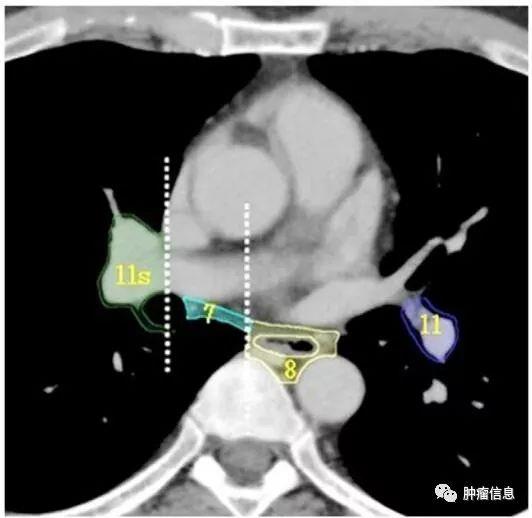

第11组淋巴结

第11组即肺叶间淋巴结,位于支气管分叉处。左侧第11组淋巴结位于第二隆突的下方。右侧的第11组淋巴结又区分为11s(右侧上叶支气管和中间支气管之间)和11i(右侧中叶支气管和下叶支气管之间)。